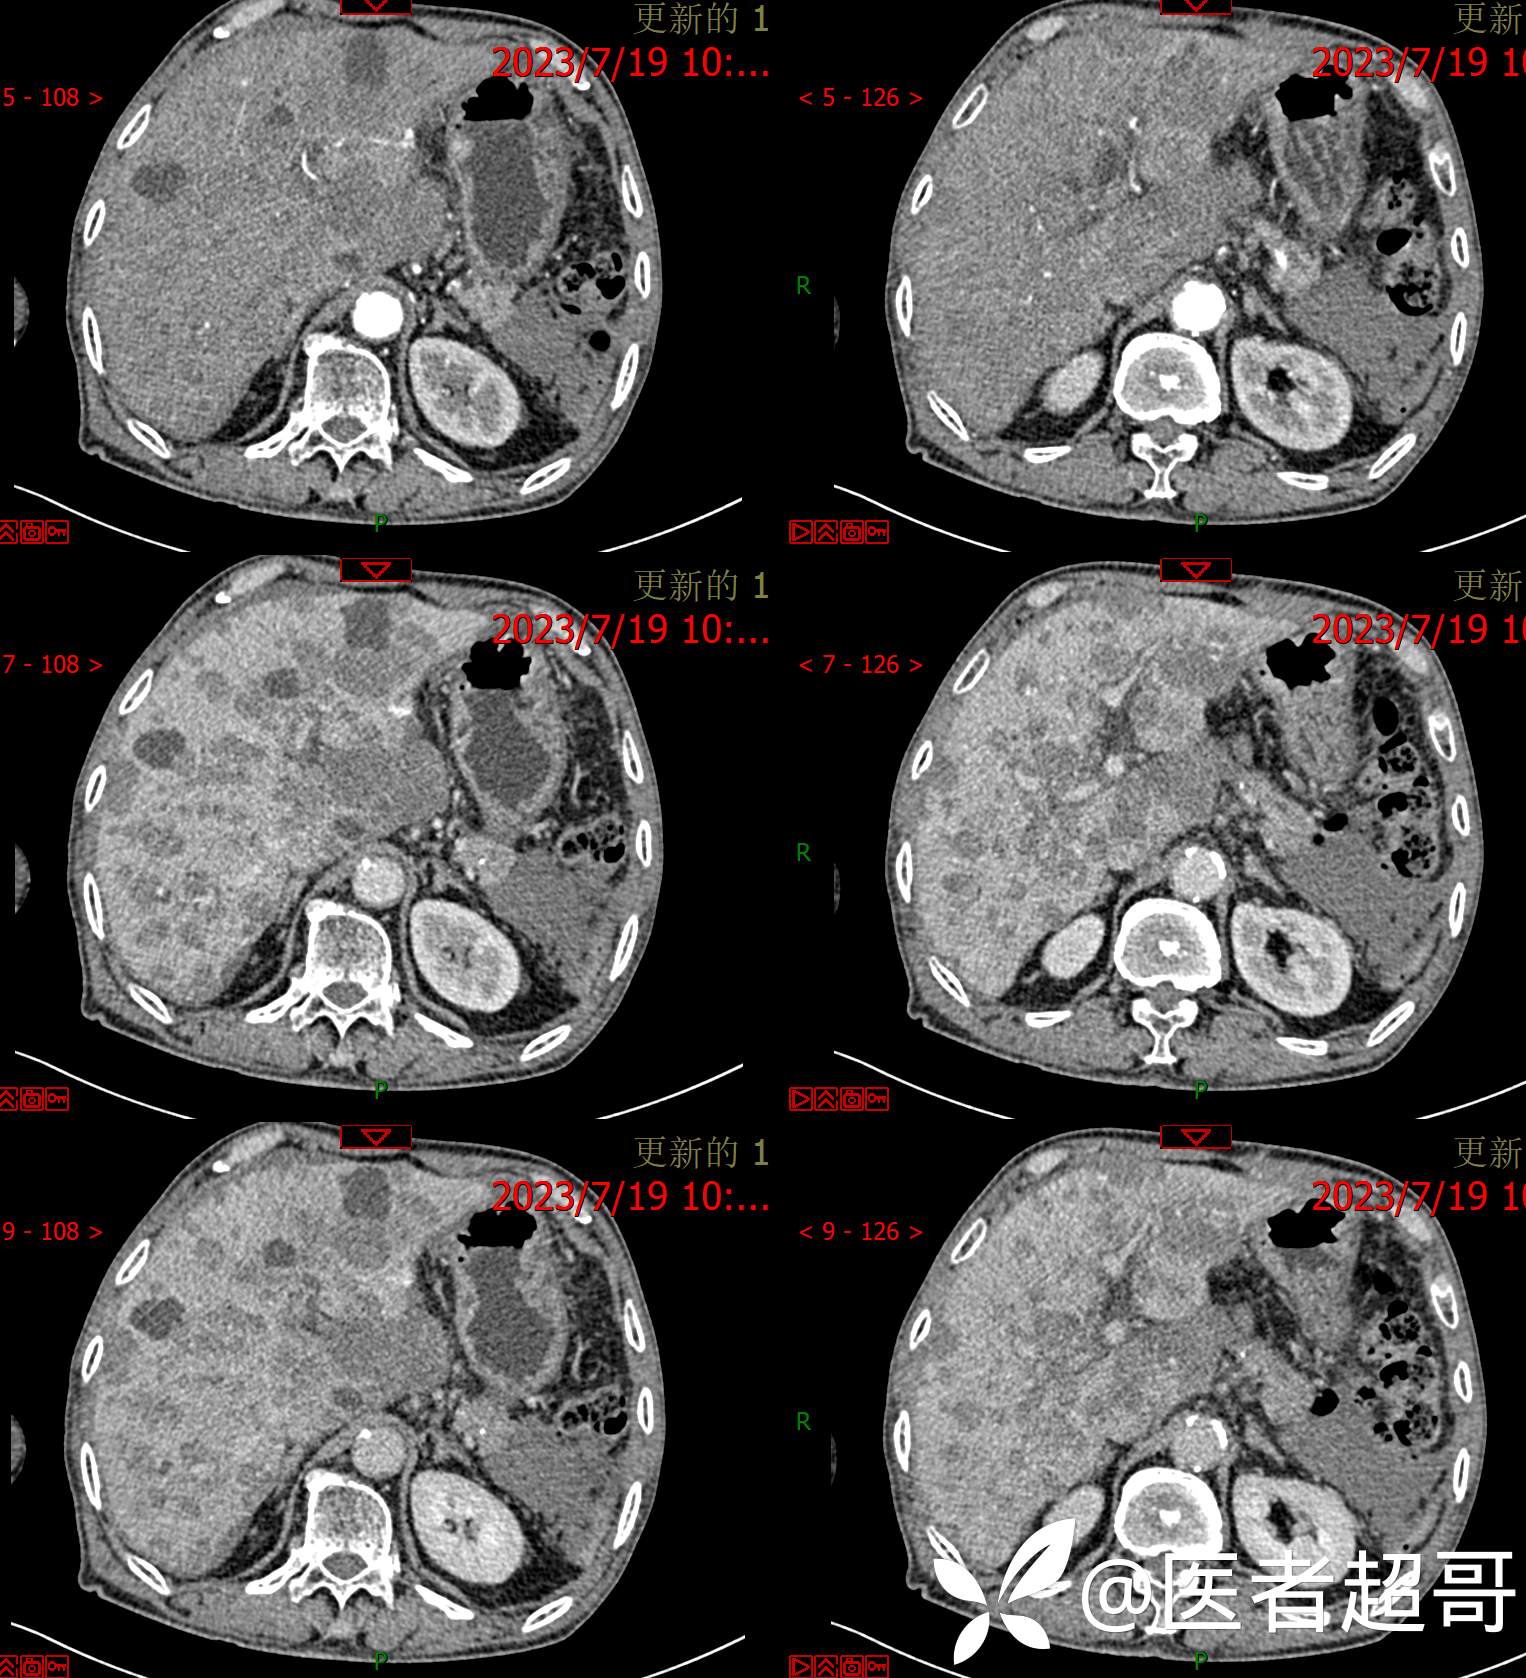

术后三个月复查CT、MRI表现:

转移性肝癌 (39)